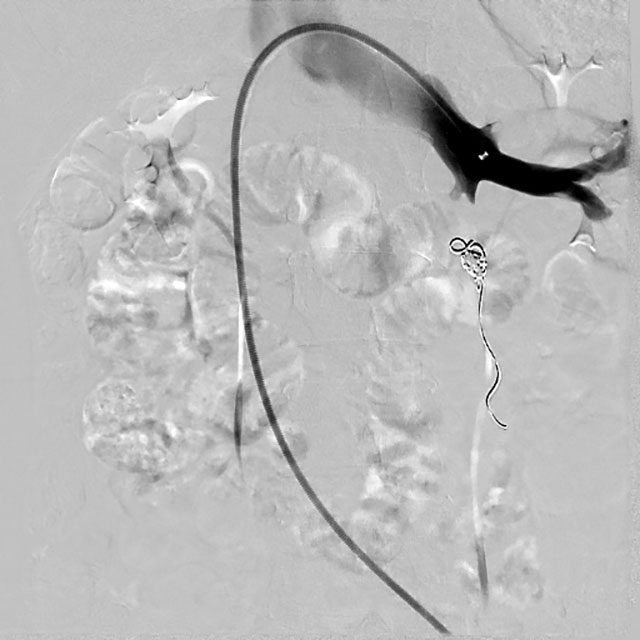

△给于硬化、栓塞后造影提示,卵巢静脉返流消失

入院后,超声检查进一步明确 “盆腔内探及曲张静脉”。介入・血管科徐燕能博士团队结合检查结果,为其制定了周密的介入手术方案 ——卵巢静脉造影 + 栓塞术。术中栓塞前的 DSA 造影显示,王女士存在 “卵巢静脉返流、迂曲” 的典型病变;而经过硬化、栓塞治疗后再次造影,卵巢静脉返流现象完全消失。